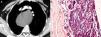

En la radiografía de tórax se demostraba la presencia de una masa mediastínica derecha que desplazaba la tráquea en dirección anterolateral. La esofagografía con contraste demostraba el desplazamiento lateral derecho del esófago cervical y mediastínico superior. Se efectuó una tomografía computarizada (TC) torácica con medio de contraste en la que se demostró la presencia de una gran masa (12×14cm) mediastínica sin realce de contraste, localizada en el compartimiento posterior visceral, que originaba el desplazamiento anterior de los grandes vasos y la tráquea y un desplazamiento anterolateral derecho del esófago (fig 1A).

A) La tomografía computarizada del tórax con medio de contraste demuestra una gran masa mediastínica (12×14cm) sin realce de contraste que provoca el desplazamiento anterior de los grandes vasos y la tráquea y el desplazamiento anterolateral del esófago. B) El examen histopatológico reveló la pared pseudoquística, que incluía tejido paratiroideo hipercelular (tinción con hematoxilina-eosina, magnificación original ×400).

Se estableció un posible diagnóstico clínico de quiste paratiroideo. Se programó su exéresis quirúrgica a través de un abordaje toracotómico sin aspiración preoperatoria del quiste con aguja fina para reducir a un mínimo el riesgo de mediastinitis y/o hemorragia no controlada en el espacio pleural. La estrategia quirúrgica excluía la cirugía torácica videoasistida (video assisted thoracic surgery [VATS]) debido a las dimensiones del quiste. Seleccionamos una toracotomía posterolateral clásica con preservación muscular, que nos permitió la exéresis completa del quiste con respecto a todas las demás estructuras mediastínicas. El examen histopatológico reveló una pared pseudoquística que incluía tejido paratiroideo hipercelular (fig. 1B).